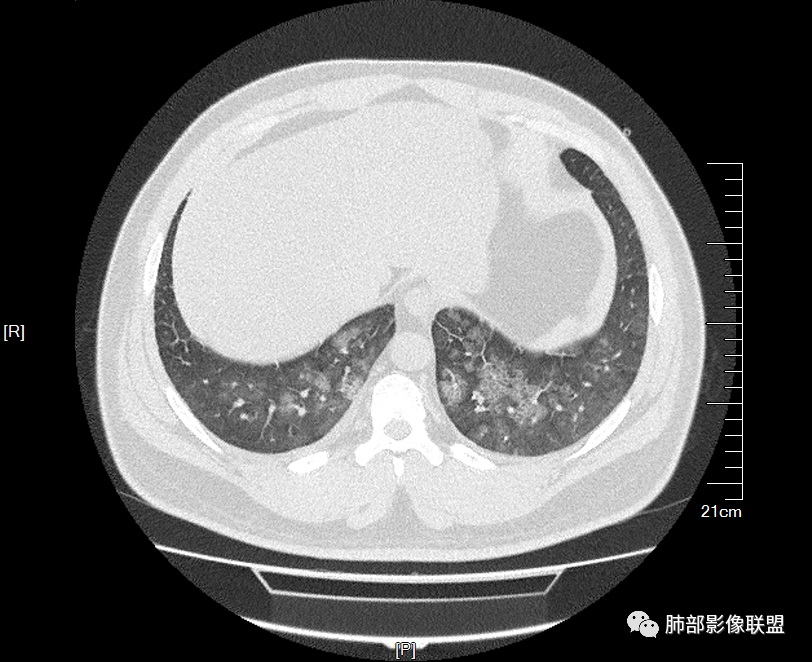

两肺弥漫向心分布的腺泡结节,部分融合,两肺小叶间隔增厚,血肌肝高,考虑肺泡性肺水肿

青年男性,有肾功能不全史和痛风史,这个影像分布有个典型的特点,全部是以中央间质周围的渗出性改变,这个改变主要就是两种可能,一种是肾功能不全导致的血管通透性增高导致的肾性肺水肿,一种是出血导致的DAH改变,具体是哪种,影像上不好简单的鉴别,需要结合更多临床资料综合分析。

年轻男性,痛风,肌酐高,提示肾功能有损,两肺多发磨玻璃腺泡结节,小叶间隔增厚,双侧少许胸水,血管增粗,考虑肾性肺水肿,DAD,鉴别肺肾综合征,需要更多临床资料

少量积液,脂肪肝

这里有一点重力趋势

中轴间质增厚,小叶间隔增厚,小叶内间质增厚,部分重力作用,双侧对称,胸水,按理淋巴道回流受阻有

肺水肿类病变有

问题是腺泡结节如何解释?

一般吸入性病变,肺泡腔充填性病变